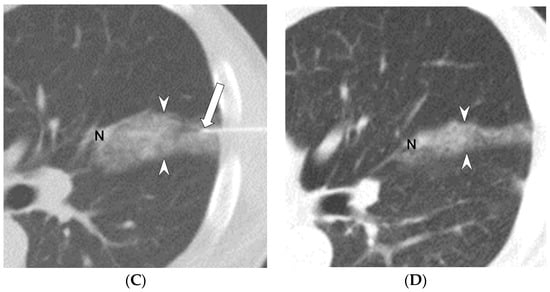

2.2. Methods for CT-Guided Localization with PBV Dye